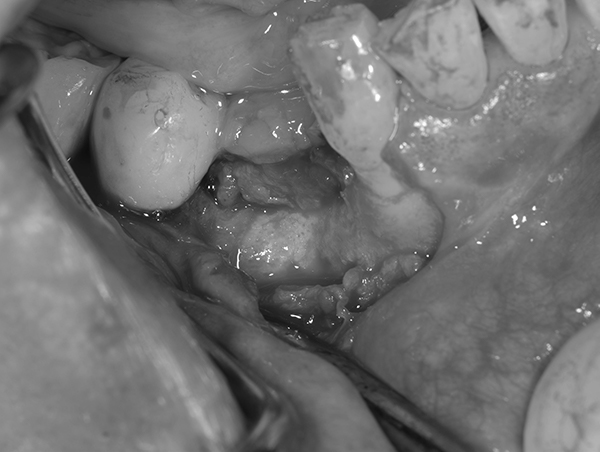

インプラント予定部位の骨の状態。 骨のてっぺんの部分は骨が薄く、また、横には大きな穴があいている状態。 これではインプラントを埋めてもしっかり入らずに、骨から飛び出してしまう。

麻布十番歯科のインプラント予定部位の骨の状態の症例写真

そのため、骨をてっぺんと穴の空いた部分に作る。 そのために、人工の骨をおき、チタンのメッシュで固定する。 この状態で6ヶ月ほど待機する。

麻布十番歯科のインプラント治療で人工の骨をおき、チタンのメッシュで固定している症例写真